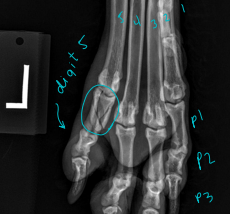

Digits & Metacarpal/Metatarsal Bones

Check each digit/nail bed and webbing

Pain, abnormal size, foreign material, draining tracts

Flex/extend phalangeal joints

Carpal, Metacarpal, Digital, Metatarsal Fractures

Very common, greyhounds

Carpal: lag screw

Metacarpal and Metatarsal: medical tx most common

Tx: closed reduction + caudal splint (Rx #1), IM pins/plates + caudal splint (Sx)

Sx indicated if open, grossly displaced, intra-articular, or all 4 fractured

Digital: caudal splint bandage for 6w